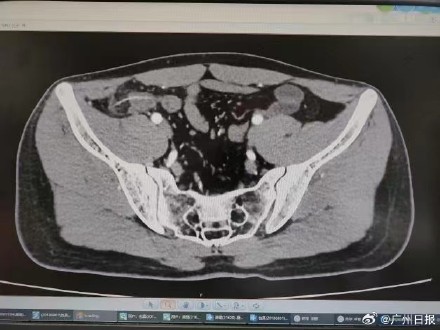

克日,19岁的年夜先生小冯在与同窗会餐时失慎吞下一根鱼刺。事先他只觉得喉部稍微不适,并未在意。但是72小时后,欧洲杯app排行榜他忽然觉得右下腹剧痛。后来认为是阑尾炎发生,外地病院给他开了消炎药,但痛苦悲伤却一直加剧。终极,小冯被紧迫转诊至暨南年夜学从属第一病院胃肠外科。经加强CT检讨发明,一根3厘米长的鱼刺曾经穿透了他的肠壁,四周构成了炎性包裹。经由手术医治,现买球平台官方网站在小冯规复精良,不呈现沾染等并发症。